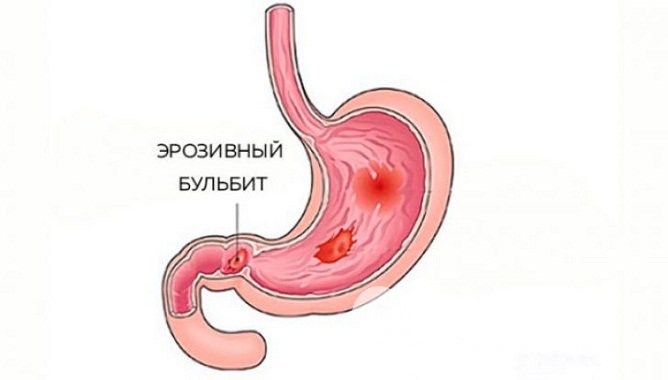

Информация и фотографии о хроническом гастрите и дуодените